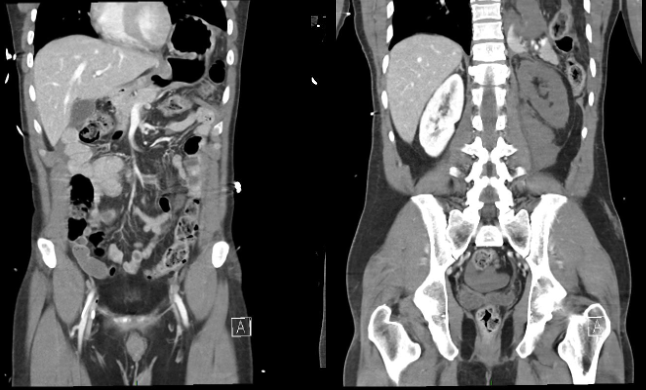

Traumatisme de l'abdomen